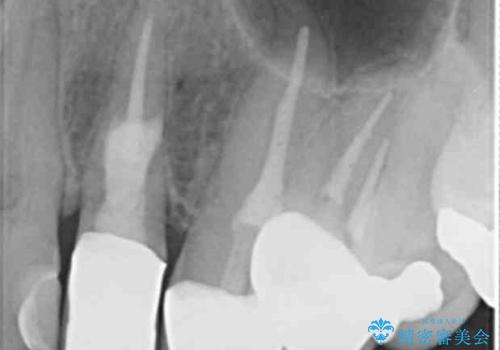

[ 根管治療・セラミッククラウン ] 噛むと痛い歯の治療

![[ 根管治療・セラミッククラウン ] 噛むと痛い歯の治療の症例 治療前](https://seimitsushinbi.jp/wp/wp-content/uploads/2021/06/CI3-500x350.jpg?v=1623381808)

![[ 根管治療・セラミッククラウン ] 噛むと痛い歯の治療の症例 治療後](https://seimitsushinbi.jp/wp/wp-content/uploads/2021/06/CI12-1-500x350.jpg?v=1623381811)